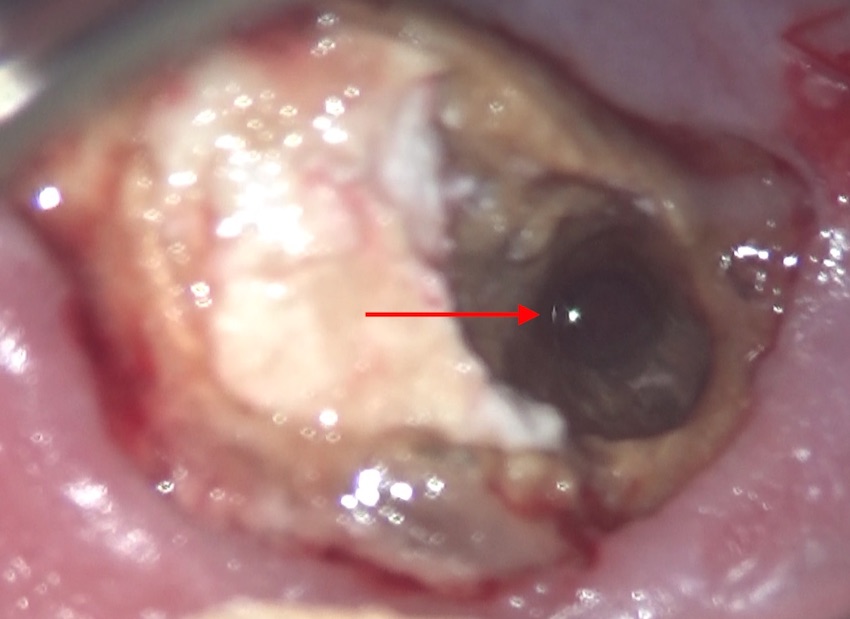

赤い→で示したのがそうです。

術前のCT画像からも分かっていたのですが、この大きな穴の中には、前医の入れてしまったファイバーポストのカケラが落ちているのが分かっていましたので、特殊な器具で内部を探ると、

内部からカケラが出てきました。取り出せて良かったです。